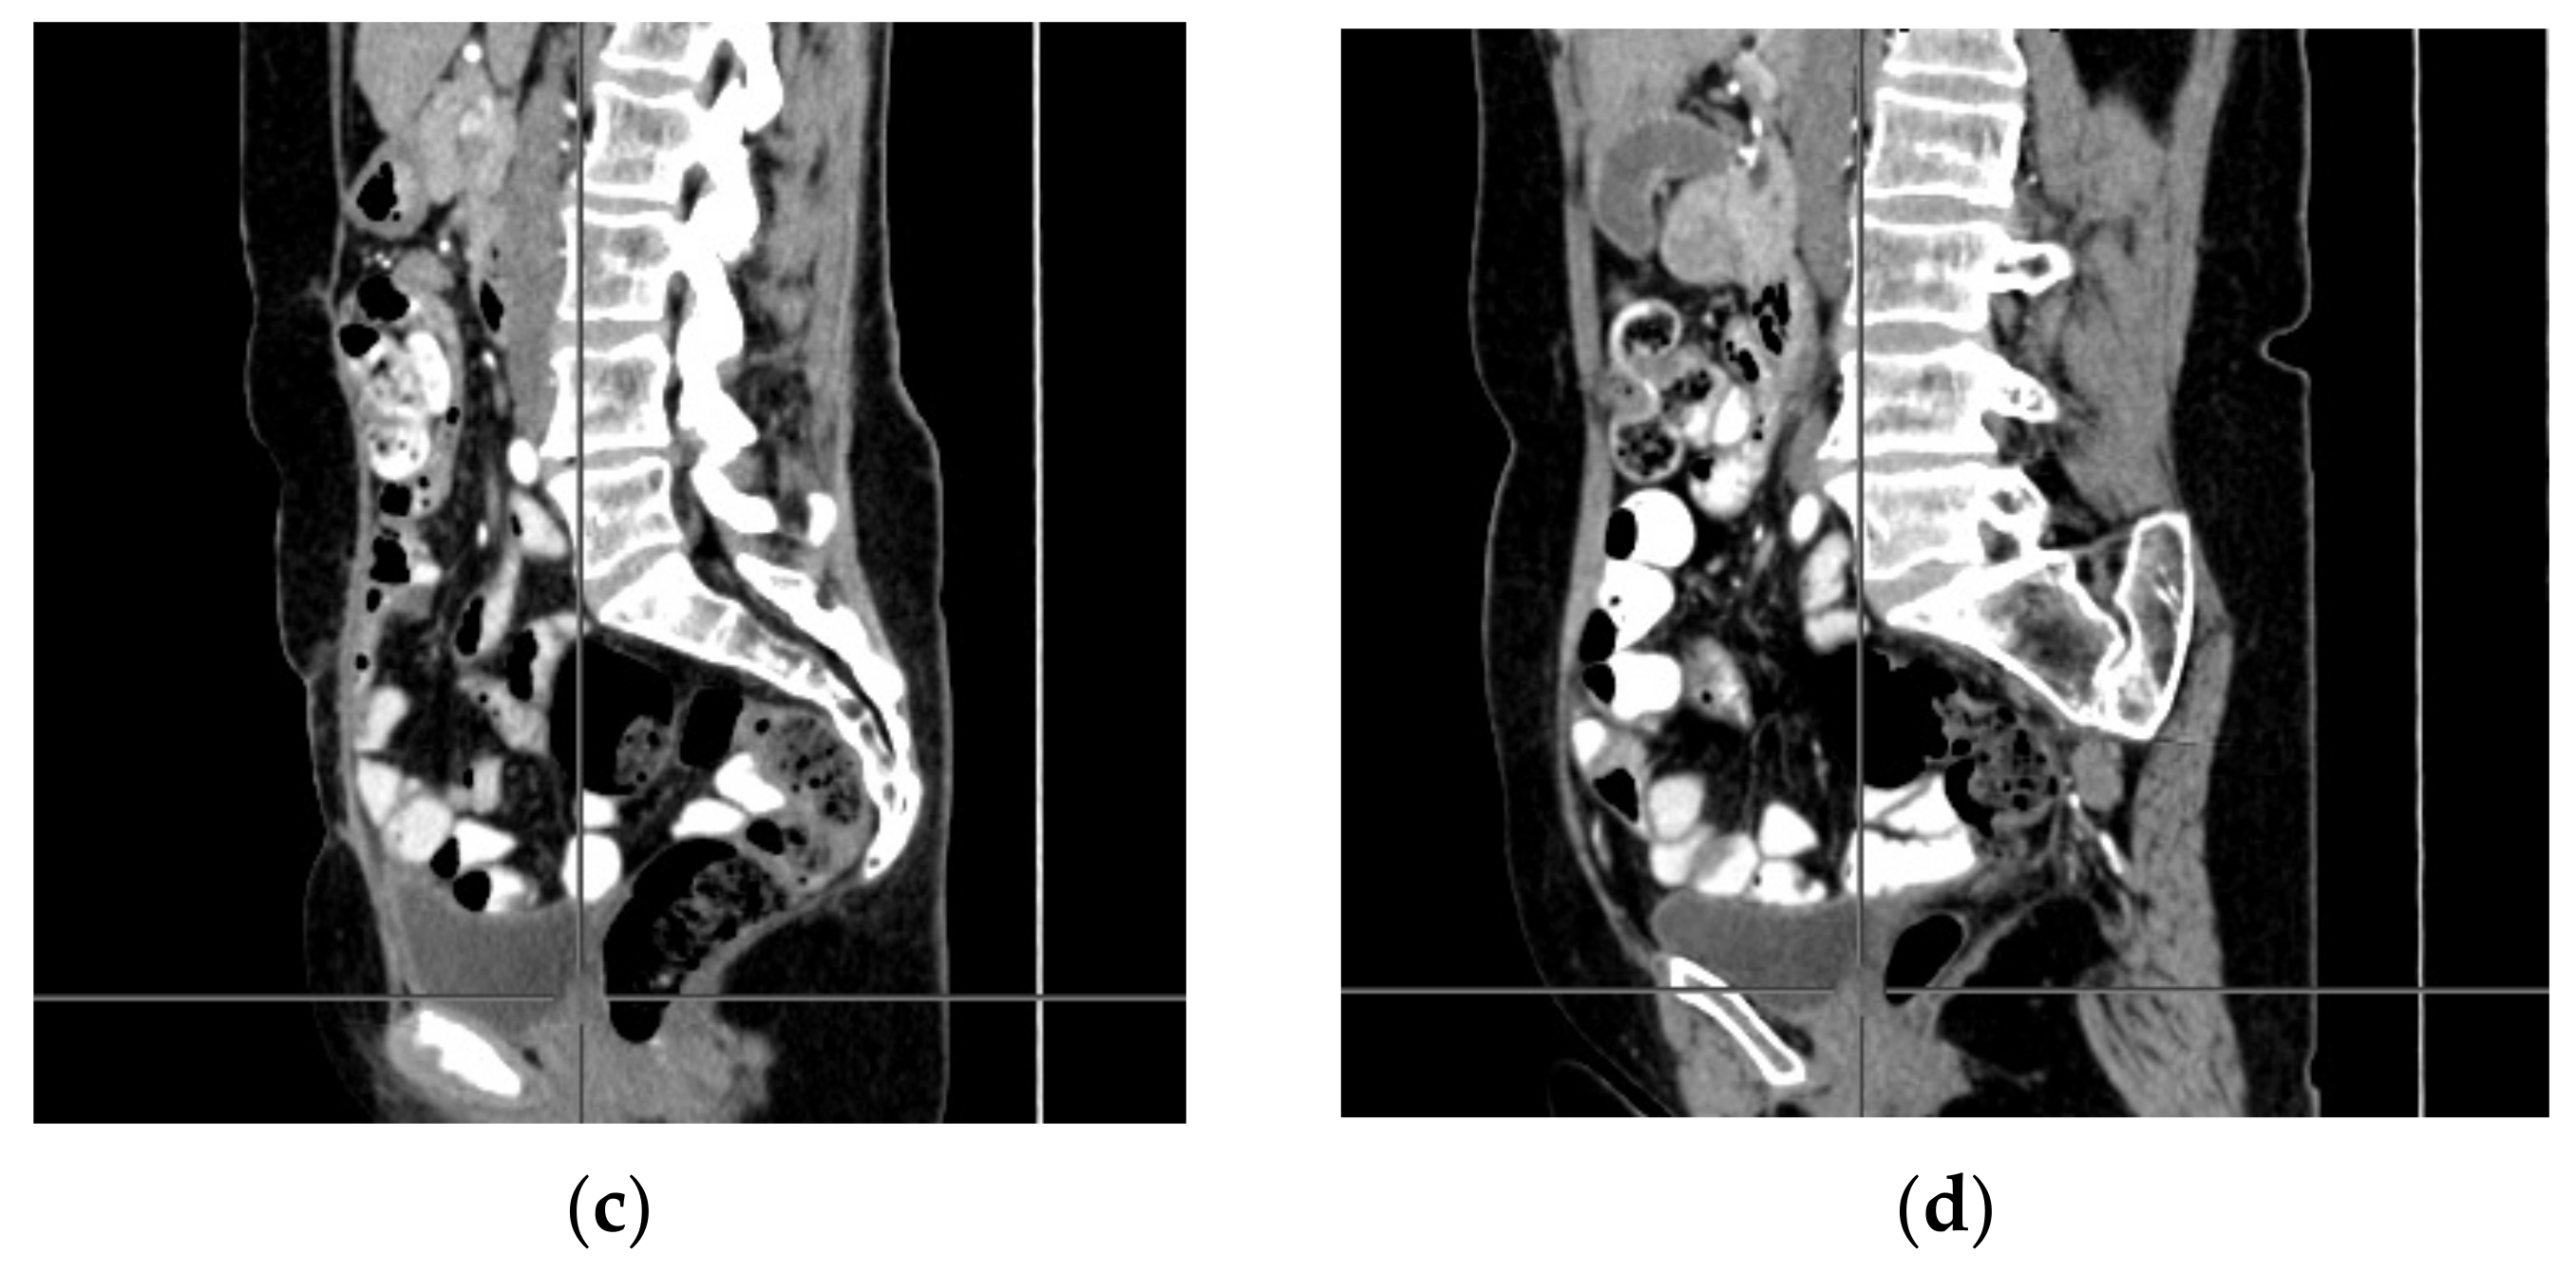

A computer tomography of the abdomen and pelvis was also performed every 3 months for the possible detection of ovarian cancer recurrence. No CT changes suggestive of recurrence were observed in the patient during the treatment. There are illustrates scans on the same section from CT performed at the beginning of PARP inhibitor treatment (Figure 2) and before 48 cycle of olaparib chemotherapy (Figure 3).

Figure 3. (ad) CT scans performed before 48 cycle of olaparib treatment.